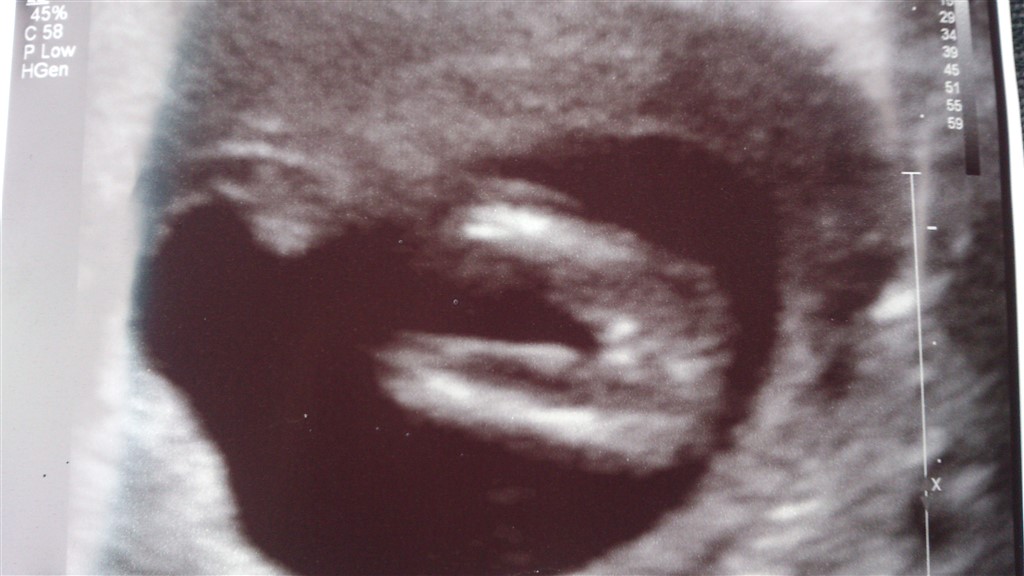

Er dette med sikkerhed en pige?

Jeg er 14+6 i dag

Nu er jeg ikke sonograf, men det ligner da de scanningsbilleder jeg har set af piger, og det ligner i hvert fald ikke det jeg fik af min søn hvor man tydligt kan se tappen

Det var en meget hurtig scanning.. Faktisk mere en tryghedsscanning.. Og han sagde at det lignede en pige...

Vil bare høre jeres mening, hvis det er okay

Jeg synes bestemt det ligner en pige Tillykke med hende.

Tillykke! Det ligner en lille pige

Det ligner en pige, tillykke